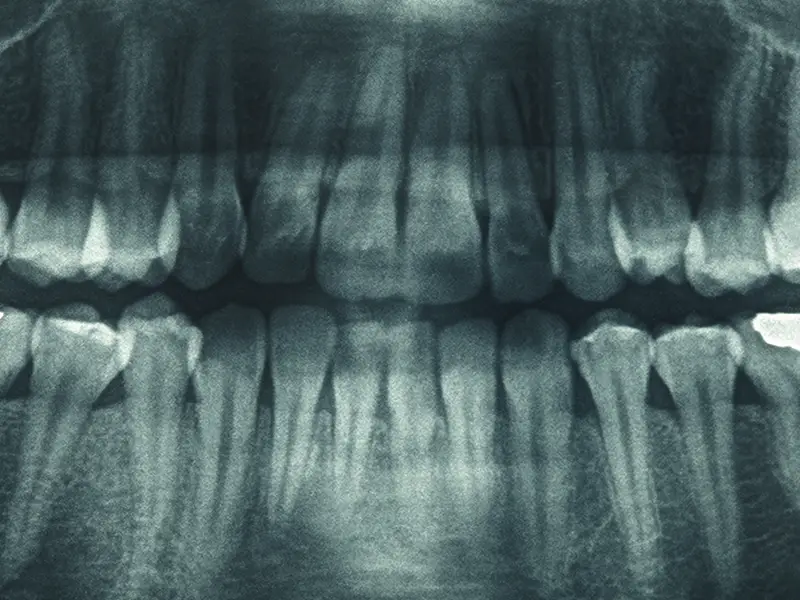

Gli esami radiologici permettono di visualizzare ciò che non è visibile a occhio nudo: radici, osso mascellare, articolazioni e tessuti circostanti. Una diagnosi corretta dipende dalla qualità delle immagini, per questo nello Studio Dentistico Baragazza a Castiglione dei Pepoli utilizziamo dispositivi digitali di ultima generazione, pensati per garantire massima precisione con la minima esposizione possibile.

La panoramica dentale offre una visione completa di denti, mascella e mandibola in un’unica immagine. È un esame rapido e indolore, ideale per avere un quadro generale della situazione orale.

Viene utilizzato per valutare lo stato parodontale, lesioni periapicali e carie interprossimali difficili da individuare clinicamente, controllare lo stato delle otturazioni e monitorare la permuta dentale nei pazienti più giovani.

L’utilizzo della tecnologia digitale riduce al minimo l’esposizione alle radiazioni e fornisce immagini nitide, facilmente condivisibili durante la visita.

Radiografia endorale: dettagli ad alta definizione

Grazie alla radiografia endorale possiamo acquisire radiografie mirate su singoli denti o piccole aree della bocca con una qualità d’immagine superiore rispetto ai sistemi tradizionali. Questo ci permette di:

- individuare precocemente carie iniziali

- lesioni tra i denti

- infiammazioni delle radici

- piccoli difetti non visibili nella panoramica.

La tecnologia digitale garantisce inoltre una minore esposizione ai raggi X e la possibilità di visualizzare immediatamente le immagini sul monitor, spiegando al paziente ogni passaggio in modo chiaro e comprensibile.